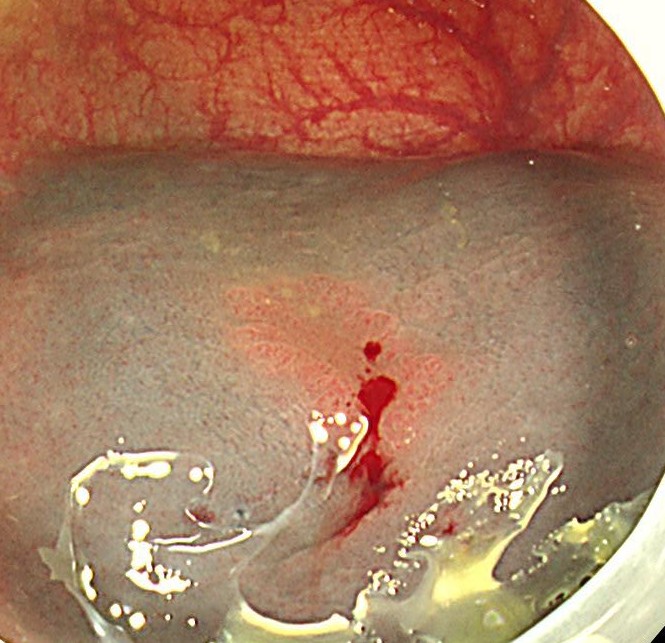

早期がんが疑われますが、内視鏡治療可能と判断しました。ムコアップ注入を用いて粘膜下をリフトアップします。